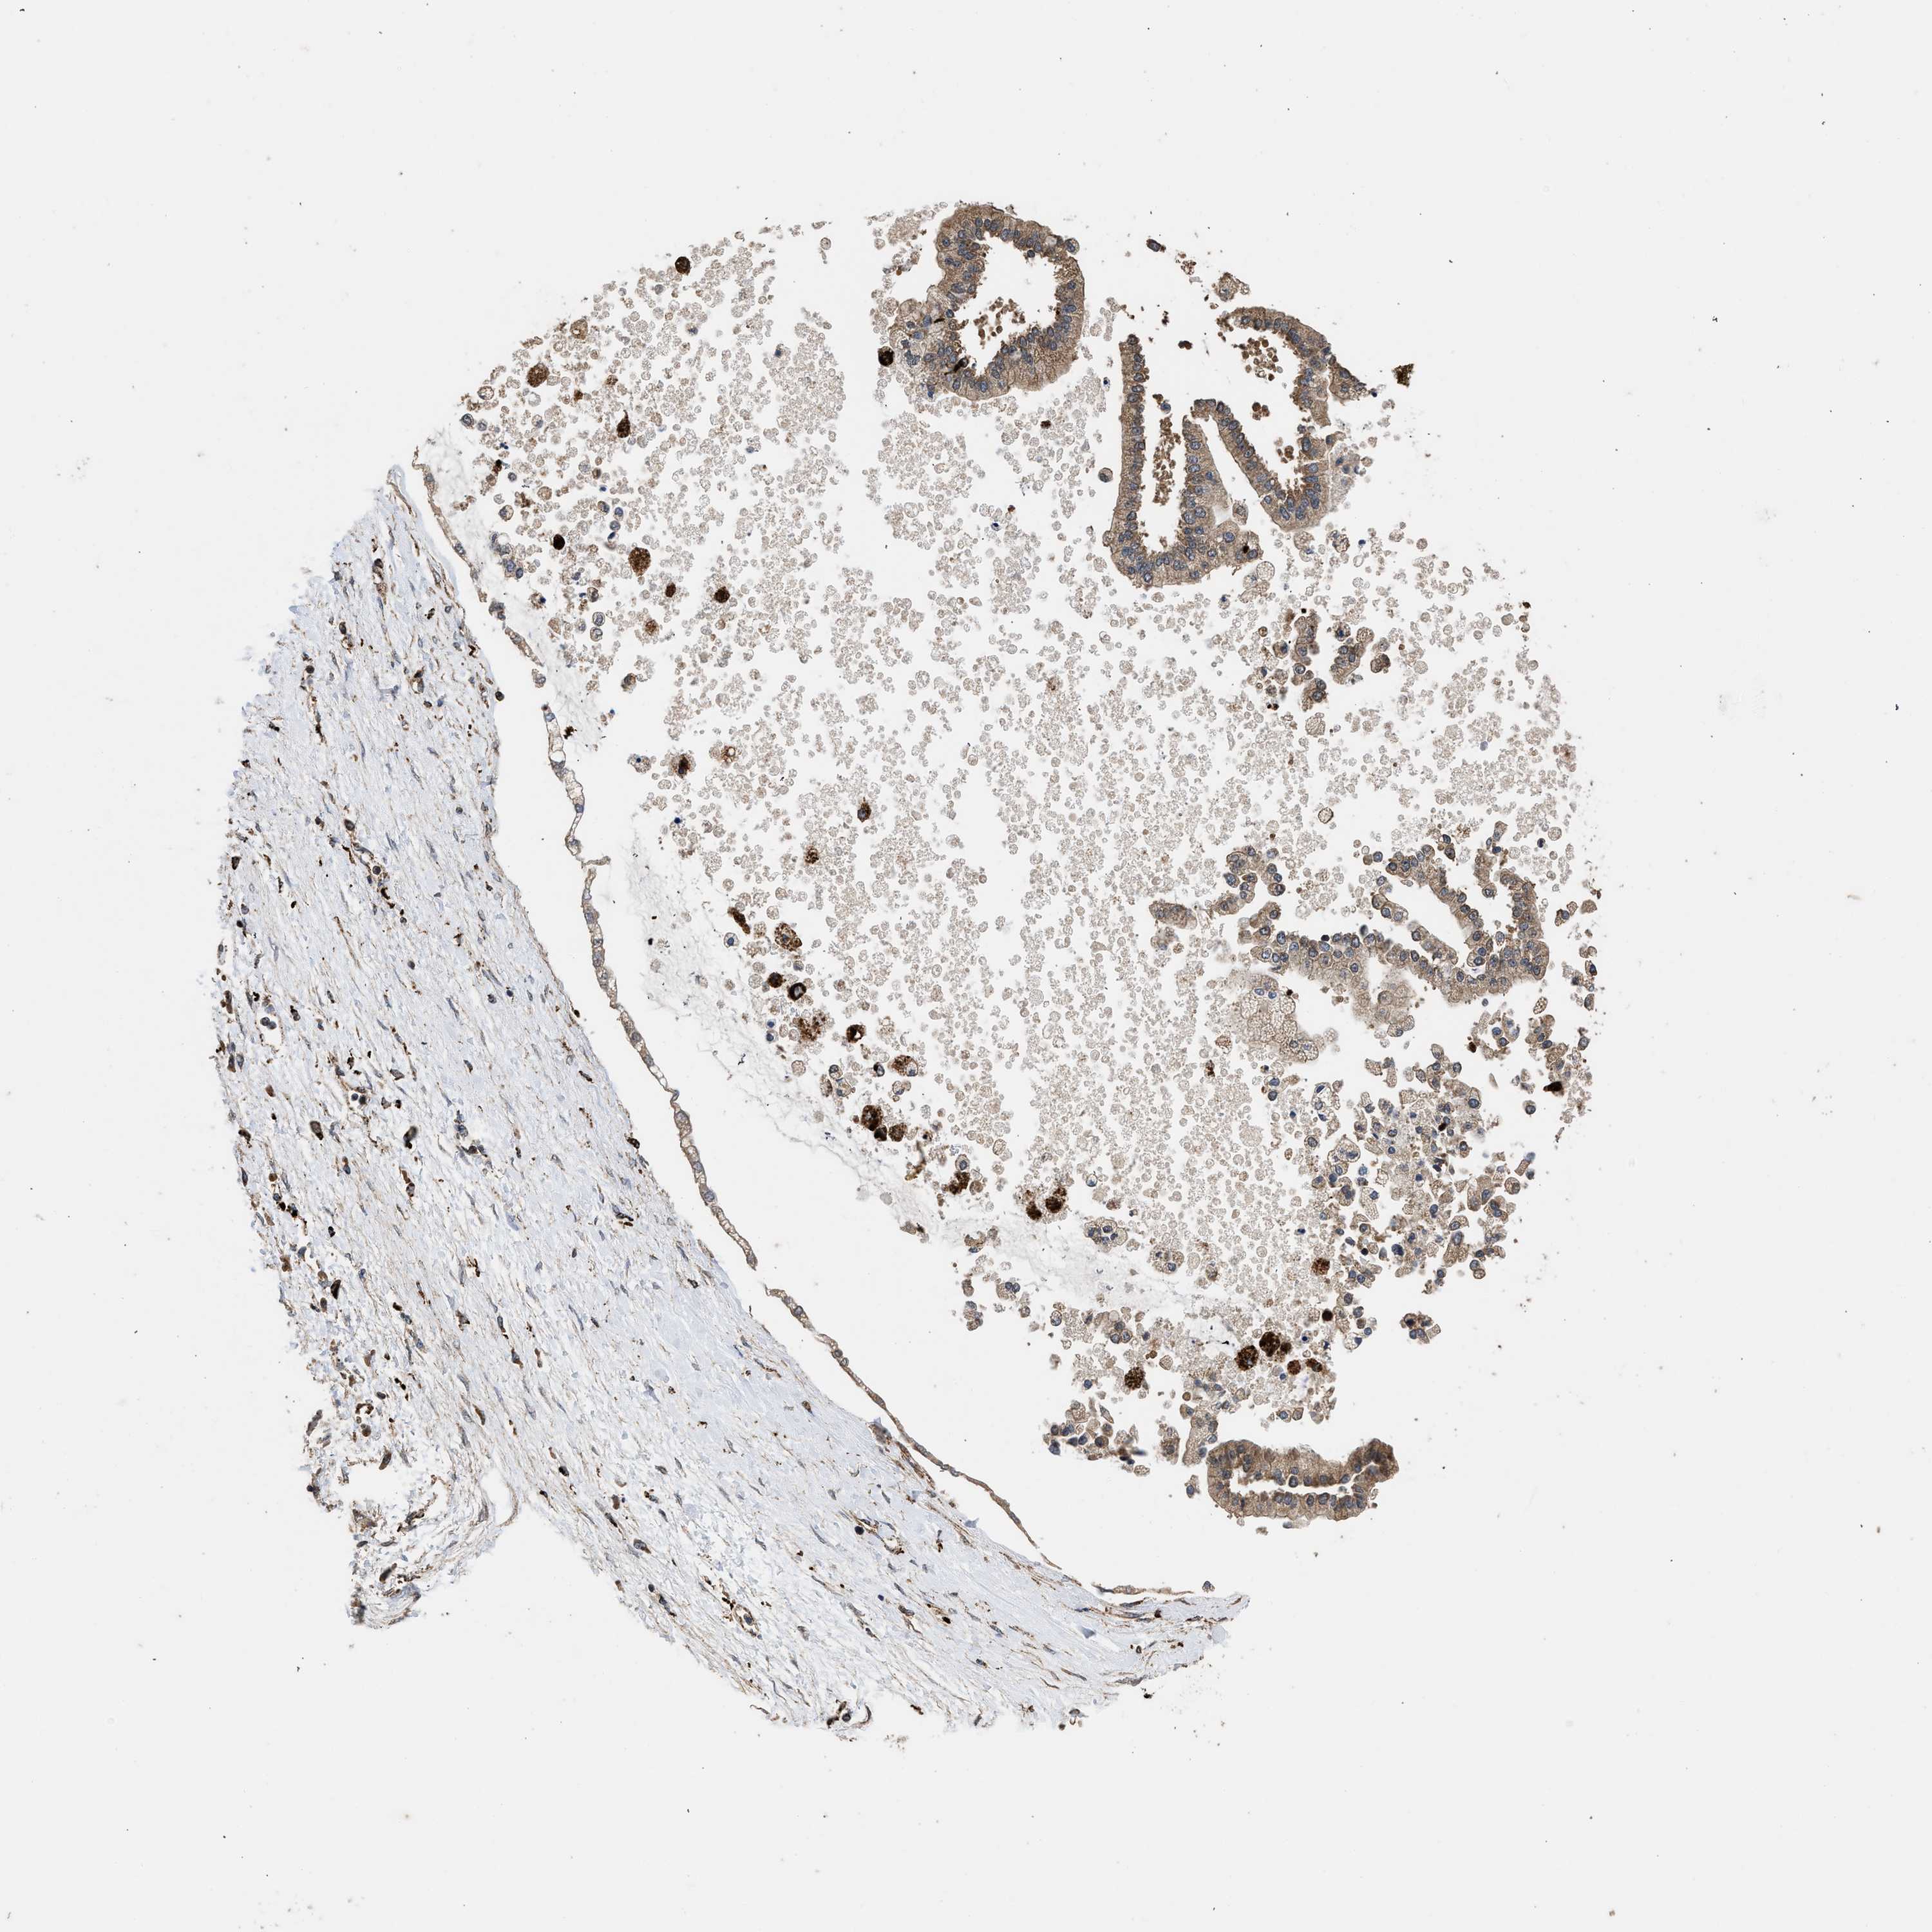

LIVER CANCER - Protein expressioni

A mouse-over function shows sample information and annotation data. Click on an image to view it in a full screen mode. Samples can be filtered based on level of antibody staining by selecting one or several of the following categories: high, medium, low and not detected. The assay and annotation is described here.

Note that samples used for immunohistochemistry by the Human Protein Atlas do not correspond to samples in the TCGA dataset.

Antibody stainingi

Antibody staining in the annotated cell types in the current human tissue is reported as not detected, low, medium, or high, based on conventional immunohistochemistry profiling in selected tissues. This score is based on the combination of the staining intensity and fraction of stained cells.

Each image is clickable and will lead to virtual microscopy that enables deeper exploration of all samples and also displays staining intensity scores, fraction scores and subcellular localization as well as patient and tissue information for each sample.

Antibody CAB017112

Staining

High

Medium

Low

Not detected

Intensity

Strong

Moderate

Weak

Negative

Quantity

>75%

75%-25%

<25%

None

Location

Nuclear

Cytoplasmic/membranous

Cytoplasmic/membranous,nuclear

Cholangiocarcinoma

Carcinoma, Hepatocellular, NOS